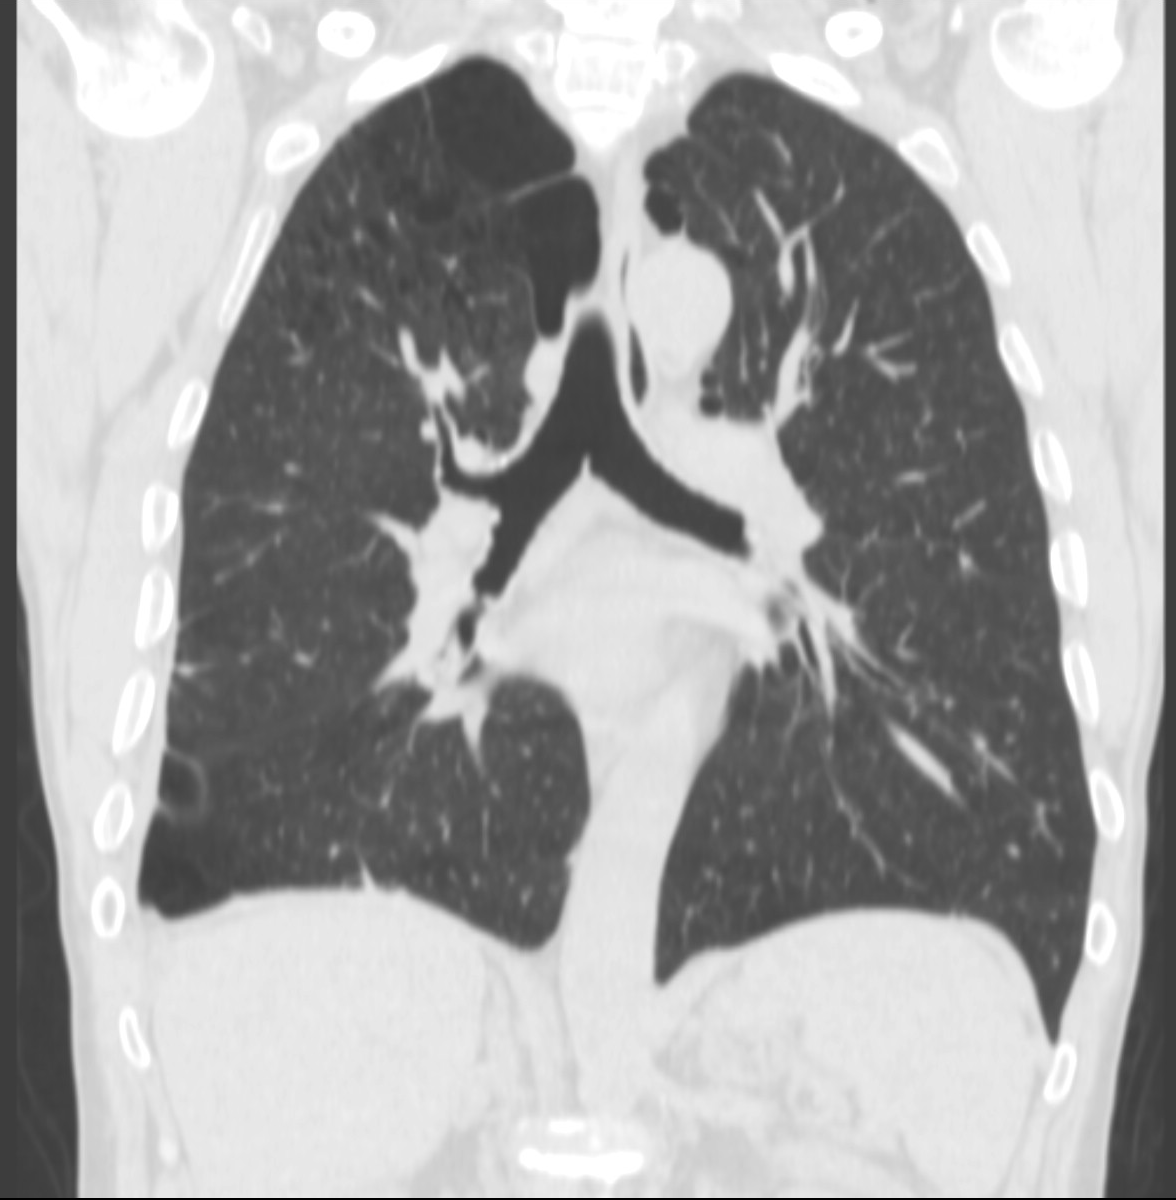

20. Miliary lung metastases. HRCT, coronal reconstruction:

60 year old man, secondary pulmonary lesions due to kidney tumor, underwent target therapy.

Lobulated nodule in the left lung, associated with the pleura dorsobasally.

Lobectomy because of right lung adenocarcinoma, (brain metastasis). (by the contribution of Zsuzsanna Monostori, MD, PhD)